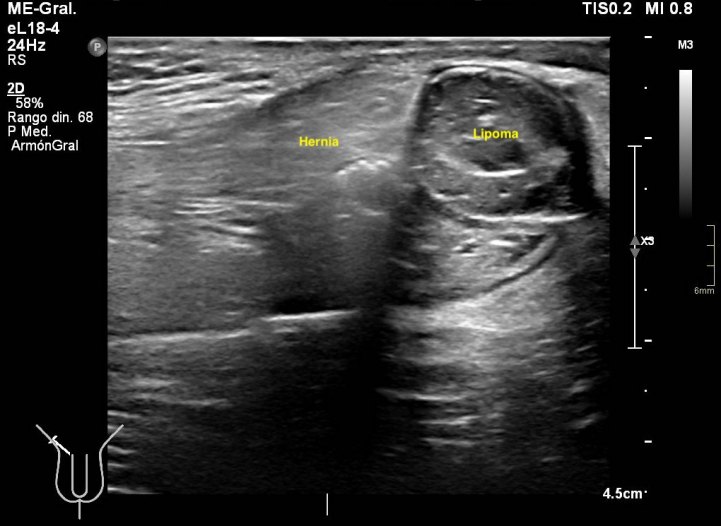

291. Lipoma de cordón y hernia inguinal.

En algunas ocasiones te encuentras cosas muy chulas, sin esperarlas, son esas cosas que no olvidas. Esta semana entró en la sala un paciente para descartar una hernia inguinal, valorada por el cirujano previa a la cirugía. Cuando el paciente se tumbó en la camilla y se descubrió la región inguinal, era evidente que algo pasaba porque tenía un bulto muy llamativo, duro. Justo cuando le puse el traductor y sin tiempo para reaccionar la hernia se corrigió, el bulto desapareció…casi. Me di cuenta que la hernia existía, sin verla, así que me pude a evaluar la región inguinal desde le teste, buscando el canal inguinal…Sorpresa…

Nada más acabar el testículo y empezar el canal inguinal me encontré una estructura hipoecogénica, con septos, con un borde ecogénico a modo de cápsula muy llamativo. La estructura era dura y fija, no respondía a valsalva, enseguida me dí cuenta de que no era parte de una hernia, no era una tripa, porque no se movía…siguiente sorpresa…

Cuando le pedía al paciente que hiciera valsalva, y por el canal inguinal aparecía una hernia muy evidente, con un cuello visible en dos proyecciones, la hernia tenía tanto grasa como asas intestinales, sonaba al entrar y al salir.

Lo más llamativo y lo que más me gustó de la prueba es que cuando la hernia llegaba a la estructura fija que estudié en primera instancia, la abrazaba, se apoyaba en ella y o conseguía moverla…y después retrocedía introduciéndose en la cavidad abdominal.

La hernia era una hernia más, el bultoma me hizo saltar las alarmas y se lo comuniqué al radiólogo responsable. Ante la sospecha razonable de que pudiera ser un tumor, decidió ampliar con un TAC de Pelvis sin CIV que demostró la existencia tumonal benigna que correspondía con un lipoma de cordón, benigno, por su aspecto amable, bordes definidos, tabique externo y centro graso.

Hernia inguinal, con foramen de 15 mm, con introduccion en saco herniario de 3 cms, de grasa omental. Imagen nodular en cordon, distal, de 2 cms, que sugiere patologia benigna.

En una misma región coexistiendo dos figuras patológicas. Fue muy bonito ver que la hernia tocaba el lipoma y retrocedía, disfruté comprobando que los hallazgos ecográficos se confirmaron con el scanner. El caso es precioso y quería que lo vieses, y en esta noche lluviosa y fría, te lo dejo en imágenes…Espero que te guste.

De la imagen 2 a la 5 puedes ver documentado y medido en dos planos con doppler la lesión fija en el cordón.

De la imagem 6 a 8 puedes ver la lesión y su relación con la hernia, en la 6, no se ve la hernia, pero sí el canal inguinal, en la 7 y la 8 observas como la hernia toca el lipoma casi abrazándolo.

La 9 demuestra el contenido de tripas en la hernia.

La 10 y la 11 como la hernia se retira paulatinamente cuando el paciente deja de hacer la maniobra de valsalva.

La imagen 12, lo que corroboraba la sospecha de lesión tumoral en el cordón a expensas de la coexistencia de una hernia en esa localización. Precioso, TODO.